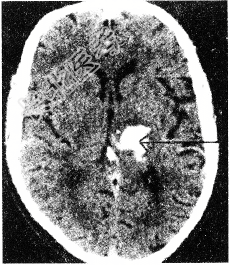

单项选择题患者,69岁。既往有高血压病史5年。因突发头痛, 右侧肢体无力1天入院。行头颅CT扫描如图所示,可诊断是

A、左尾状核

B、左丘脑出血

C、右丘脑出血

D、左壳核出血

E、左颞叶出血